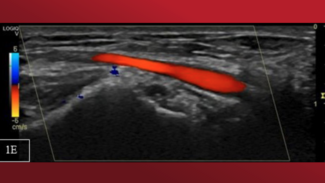

A 63-year-old man with a history of smoking, panic attacks, and positive treadmill test was referred for invasive coronary angiography (CA). By a right radial artery (RA) approach, there was difficulty advancing the sheath and the standard...